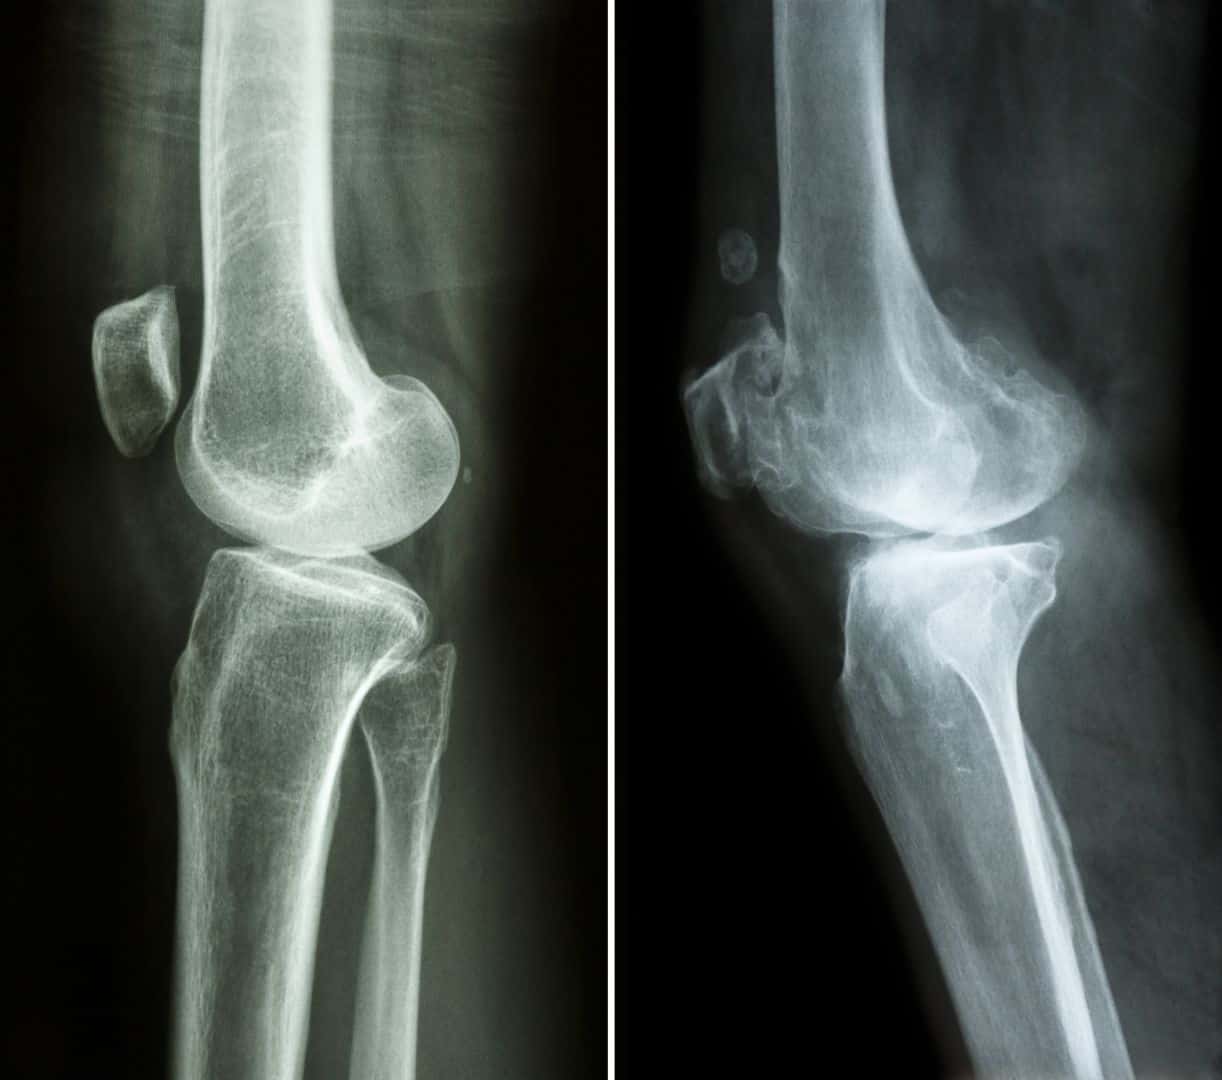

Xray Stages of Knee Arthritis YouTube Knee Injury Vs Arthritis However, there are significant differences between osteoarthritis and. Here are the key differences between the two conditions. Causes of knee pain include injury, degeneration, arthritis,. Degeneration of articular cartilage causes knee joint inflammation and increased friction. Both knee injuries tend to become more probable to occur with age; Knee osteoarthritis is a complex condition involving the gradual degeneration of the. Knee Injury Vs Arthritis.

Xrays and MRI for knee arthritis Dr. David Geier Sports Medicine Knee Injury Vs Arthritis Knee osteoarthritis is a complex condition involving the gradual degeneration of the articular cartilage that lines the knee joint and enables smooth movements at the knee. Degeneration of articular cartilage causes knee joint inflammation and increased friction. Here are the key differences between the two conditions. If your knee hurts and you're wondering what's going on, webmd explains how you. Knee Injury Vs Arthritis.

Osteoarthritis of the Knee XRay Knee Injury Vs Arthritis Knee osteoarthritis is a complex condition involving the gradual degeneration of the articular cartilage that lines the knee joint and enables smooth movements at the knee. Osteoarthritis and meniscal tears are injuries that both occur in the knees. Degeneration of articular cartilage causes knee joint inflammation and increased friction. Knee arthritis happens when the cartilage supporting your knee joint wears. Knee Injury Vs Arthritis.